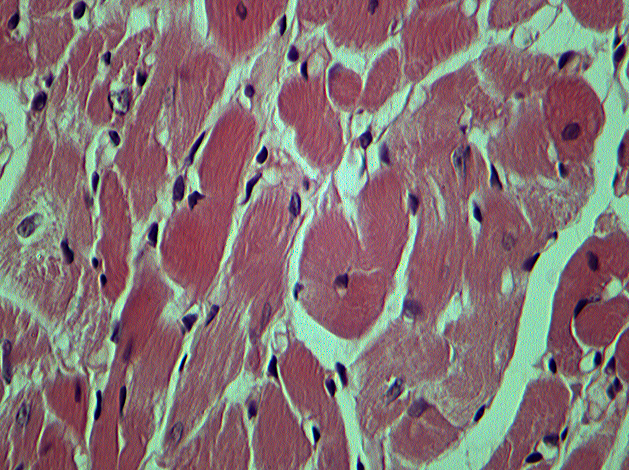

|  | 2. Рис. 1 Фрагмент миокарда ЛЖ крысы на 28 сут моделирования ЭСН. Окраска: гематоксилин Майера и эозин. Ув. об. 40, ок. 10 КМЦ с разряженной саркоплазмой и околоядерным опустошением. | |

| Тема | Фрагмент миокарда ЛЖ крысы | |

| Тип | Материалы исследования | |

Результаты. У ОЭ крыс на 14 сут ЭСН выявлены отчетливо выраженный гетероморфизм сократительных кардиомиоцитов (КМЦ) с признаками гипертрофии и дистрофии; увеличение объемной плотности (ОП) стромы, реорганизация внеклеточного матрикса (ВМ) (экспрессия металлопротеиназ-2,9 (ММП-2,9) и тканевого ингибитора металлопротеиназ-1 (ТИМП-1), КМЦ с явлениями апоптоза. После моделирования ЭСН на 28 сут в миокарде происходило дальнейшее нарастание количества КМЦ с существенно измененными морфологическими и тинкториальными свойствами, деградация компонентов ВМ миокарда. У крыс, получавших 14 сут дроспиренон, независимо от дозы, отмечался регресс патологических изменений, происходило уменьшение степени гипертрофии КМЦ и их ядер, снижение числа КМЦ с признаками апоптоза, стабилизация компонентов ВМ миокарда.